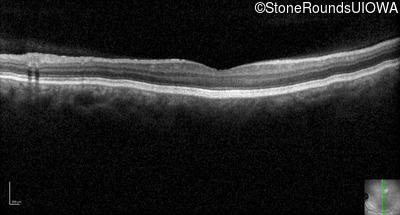

Optical Coherence Tomography - Right - 20/200

Exemplar / OCT Stack

OCT Stack